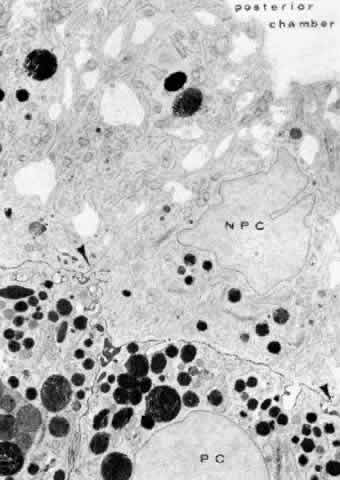

cells (see Fig. 19).  Fig. 19. Evidence of tight junctional complexes in the anterior ciliary epithelium

of Macaca mulatta. The pigmented epithelial cells (PC) are outlined

by a thin black line that is the reaction product of horeseradish peroxidase, a

tracer substance injected intravenously in vivo. The tracer

has entered the intercellular spaces of the nonpigmented epithelium (NPC) but

is held up by occluding junctions (arrowheads), preventing further

progress into the posterior chamber. (X 8450; Courtesy of Dr. Guiseppina Raviola) Fig. 19. Evidence of tight junctional complexes in the anterior ciliary epithelium

of Macaca mulatta. The pigmented epithelial cells (PC) are outlined

by a thin black line that is the reaction product of horeseradish peroxidase, a

tracer substance injected intravenously in vivo. The tracer

has entered the intercellular spaces of the nonpigmented epithelium (NPC) but

is held up by occluding junctions (arrowheads), preventing further

progress into the posterior chamber. (X 8450; Courtesy of Dr. Guiseppina Raviola)